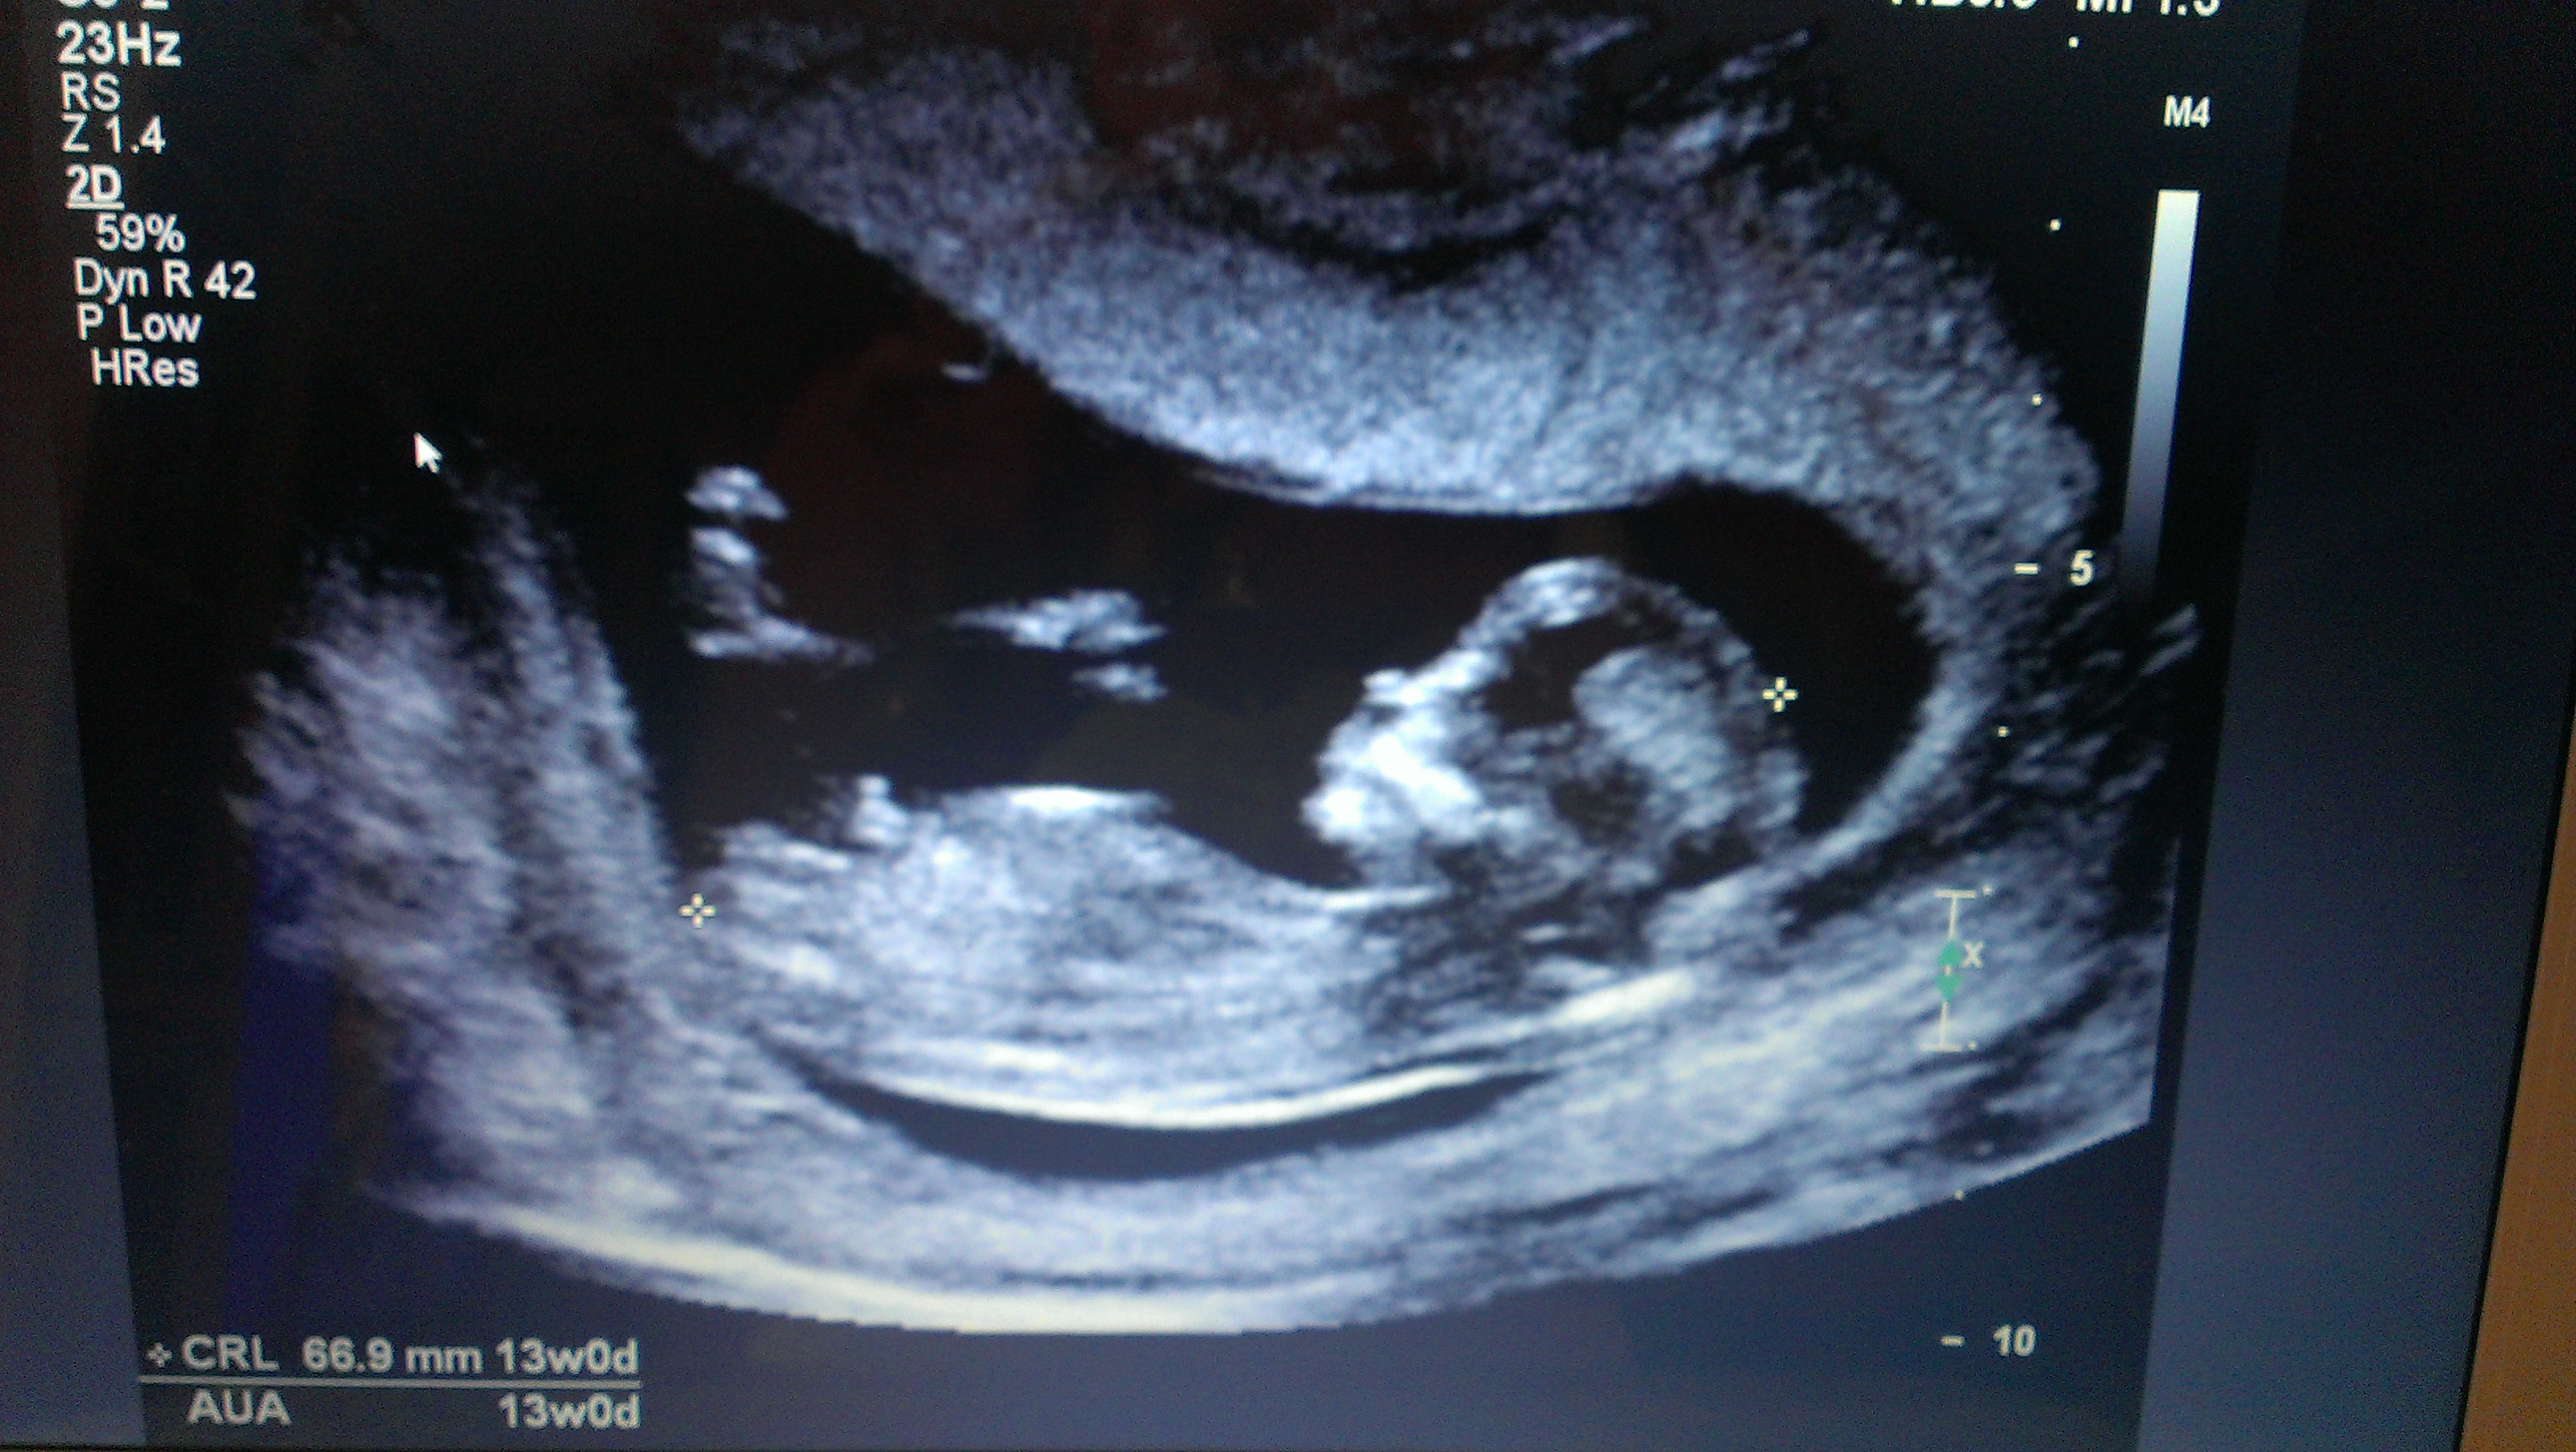

I was just going thru my disc to see if I had any other nub shots (no more unfortunately) but I think I found some potty shots.....what do you think?? Girl or boy?? Gender scan this Sunday when I'm 17w :)

And here's my best nub shot....Attachment 17810Attachment 17810

I don't see any clues in the potty shots. But I'll be surprised if the baby is a boy, based on that nub shot. It's so girly for gestation.

Thanks ladies!!! I must admit after my scan I was almost convinced it was a girl because I saw plenty of great girl nub shots throughout....but now I'm second guessing myself and almost convincing myself it's boy #3.....I supposed it's best to be prepared!! 4 days and counting until the big reveal.....eeeeeeeeekkkk!!!